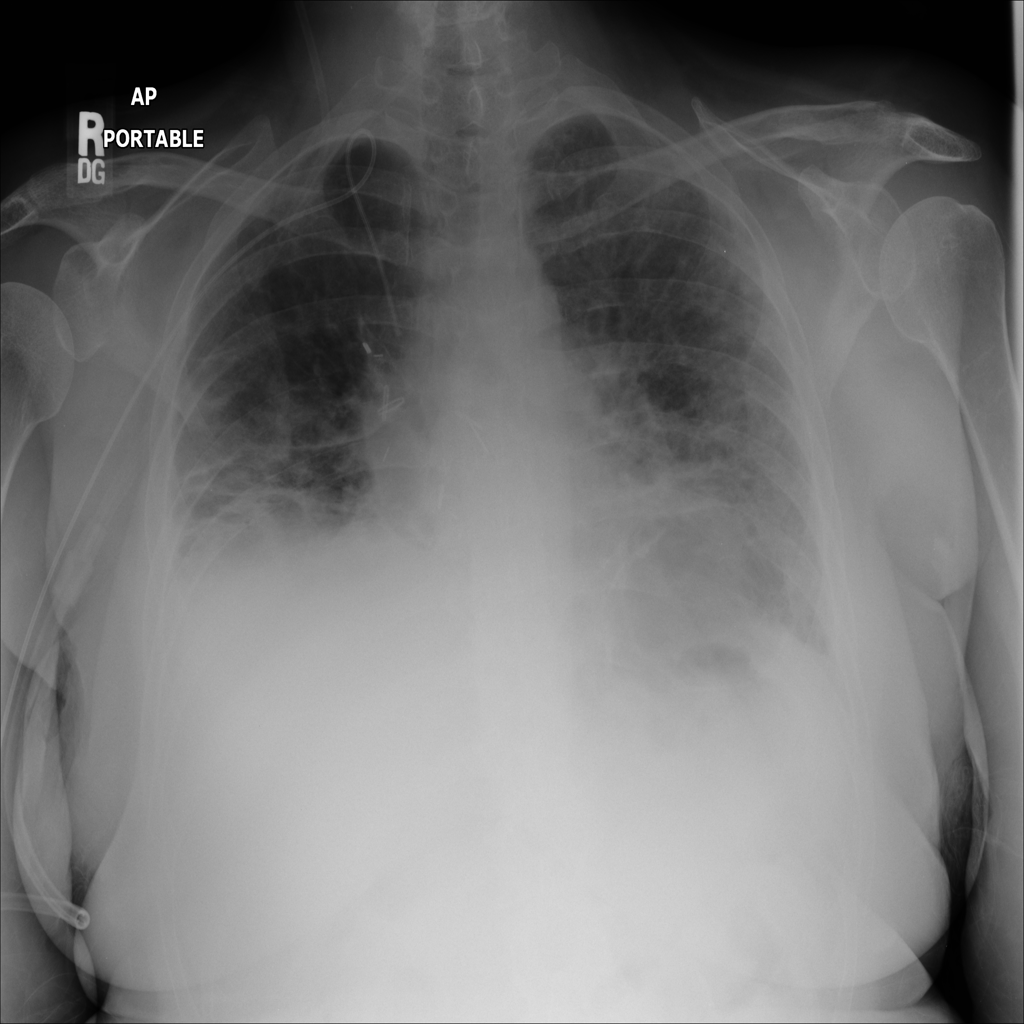

PAT-B625 · IMG-008Atelectasis

PAT-B625 · IMG-008

AP